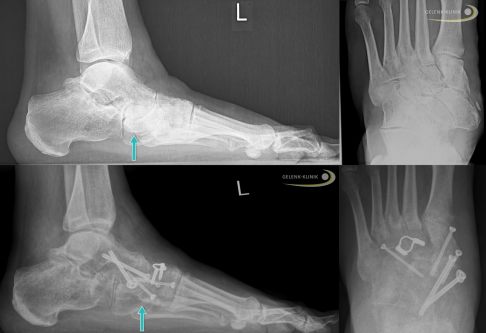

Ist das Kahnbein noch nicht zusammengesunken oder auseinander gebrochen, versucht der Spezialist, den defekten äußeren Kahnbeinanteil mit körperfremden (allogen) Knochenmaterial oder keramischen Knochen aufzufüllen und zu stabilisieren. Außerdem optimiert der Spezialist bei diesem Vorgehen immer die Stellung des Fußes. Dazu reicht es in einigen Fällen aus, die Fersenstellung zu korrigieren, ohne eine Gelenkversteifung (Arthrodese) durchzuführen.

Mögliche operative Versteifungstechniken beim Müller-Weiss-Syndrom:

Talonavikular-Arthrodese: Versteifung des Gelenks zwischen Sprungbein und Kahnbein

Triple-Arthrodese: 3-fache Versteifung aller Abschnitte des unteren Sprunggelenks:

- talocalcaneares Gelenk (Subtalargelenk) zwischen Sprungbein und Fersenbein

- Talonavikulargelenk zwischen Sprungbein und Kahnbein

- calcaneocuboidales Gelenk zwischen Fersenbein und Würfelbein

Röntgenbilder eines fortgeschrittenen Müller-Weiss-Syndroms vor OP (oben) und nach Versteifungsoperation (Arthrodese, unten). Der Kahnbeinknochen ist stark geschädigt und hat eine ausgeprägte Fehlstellung des Fußes verursacht. Der Operateur hat die Stellung des Fußes durch die Versteifung der Gelenke zwischen Sprungbein und Kahnbein (Talonavikulargelenk) sowie der Gelenke zwischen Kahnbein und Keilbeinen mittels Schrauben und Spangen korrigiert. Der Knochendefekt wurde mit Knochenspänen aus dem Beckenkamm des Patienten ausgeglichen (autologer Knochentransfer). © Gelenk-Klinik